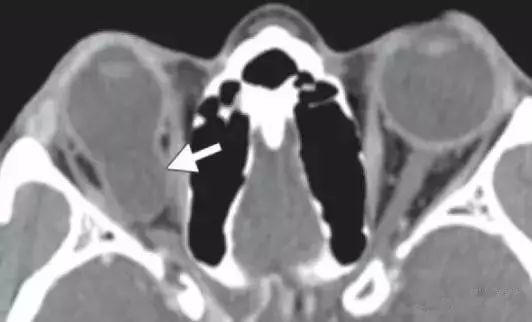

前房积血的定义是血液聚集于眼前房 , 通常由来自虹膜和睫状体的血管破裂所致 。 CT上常表现为位于前房的高密度区 。